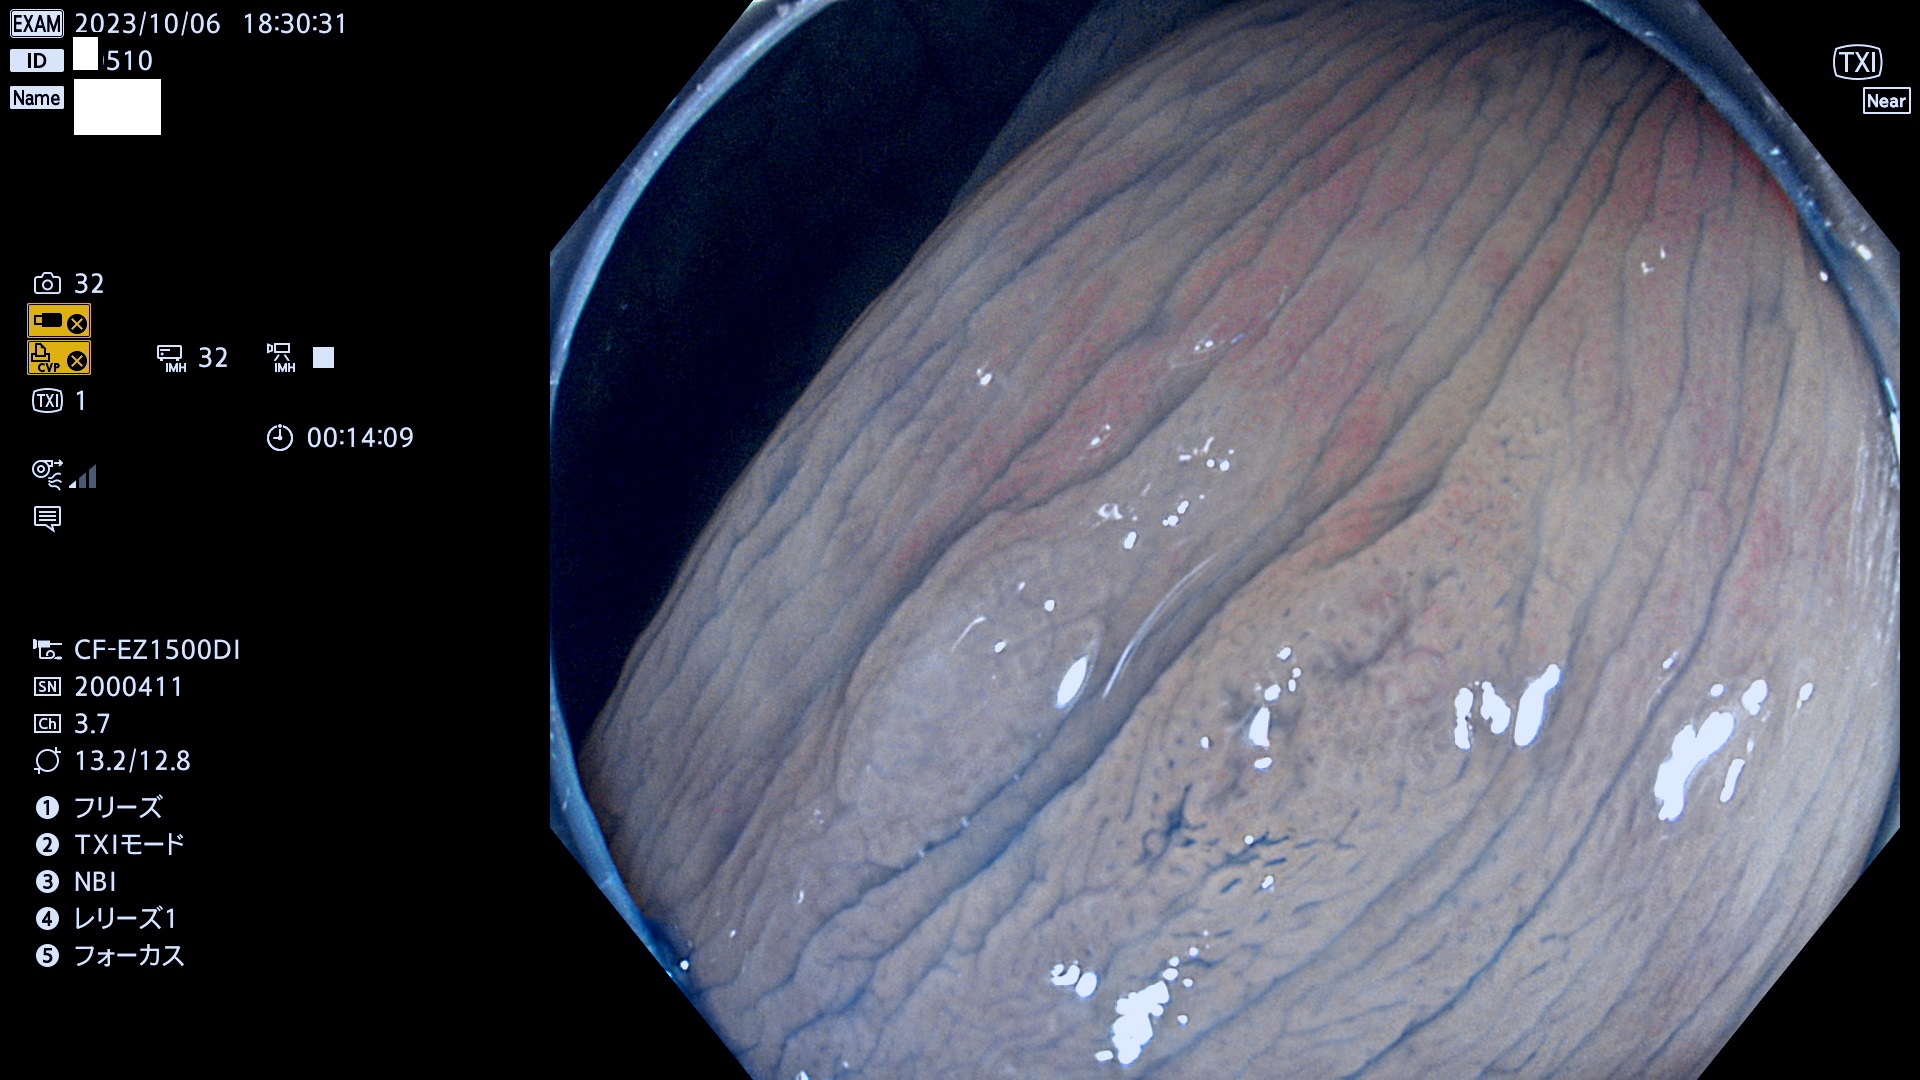

表面型腺腫(Flat Adenoma)の中で、完全に平坦な物をUb、陥凹している物をUcと呼びます。平坦隆起型(Ua)よりも、発見が難しく危険な病変です。このタイプは「内視鏡後・大腸癌の重要犯人」であり、この発見率は「腺腫発見率」よりも、重要な意味があります。

専門的)何故、陥凹していると危険? 癌遺伝子の変異が蓄積すると細胞分裂が盛んになり隆起するのでは?と通常は思われるでしょう。しかし実際は逆です。これは2022年の記事にある「細胞はストレスに直面したら細胞分裂を止める(細胞老化に入り休眠する)という生命の基本的現象」によるものです(Oncogene Stress)。細胞老化を起こすのが癌抑制遺伝子で、この安全装置(ブレーキ)が壊れると癌になります(休眠からの覚醒)。ですから陥凹は「まだ癌では無いが癌化の直前」を意味します。特に「小サイズなのに陥凹している」病変は短期間に腫瘍進化(⇒2021年記事)が起きたことを意味します(=ゲノム不安定性

専門的)Uc=De Novo癌? 内視鏡の解像度が低かった時代、このような説もありました。しかし今日の高精度内視鏡では良性の微小なUc型腺腫が日常的に見つかります。私見ですが「Ucこそが多段階発癌(Adenoma-Carcinoma Sequence)のMain Route」と考えます。

毎週の検査(木・金・土・日)に発見されたUb、Uc型・腺腫を、その週の日曜の夜にUPし1週間、提示します。

抽出の対象期間 2023年10月4日(木)〜10月9(月)の5日間(60件の検査)8件